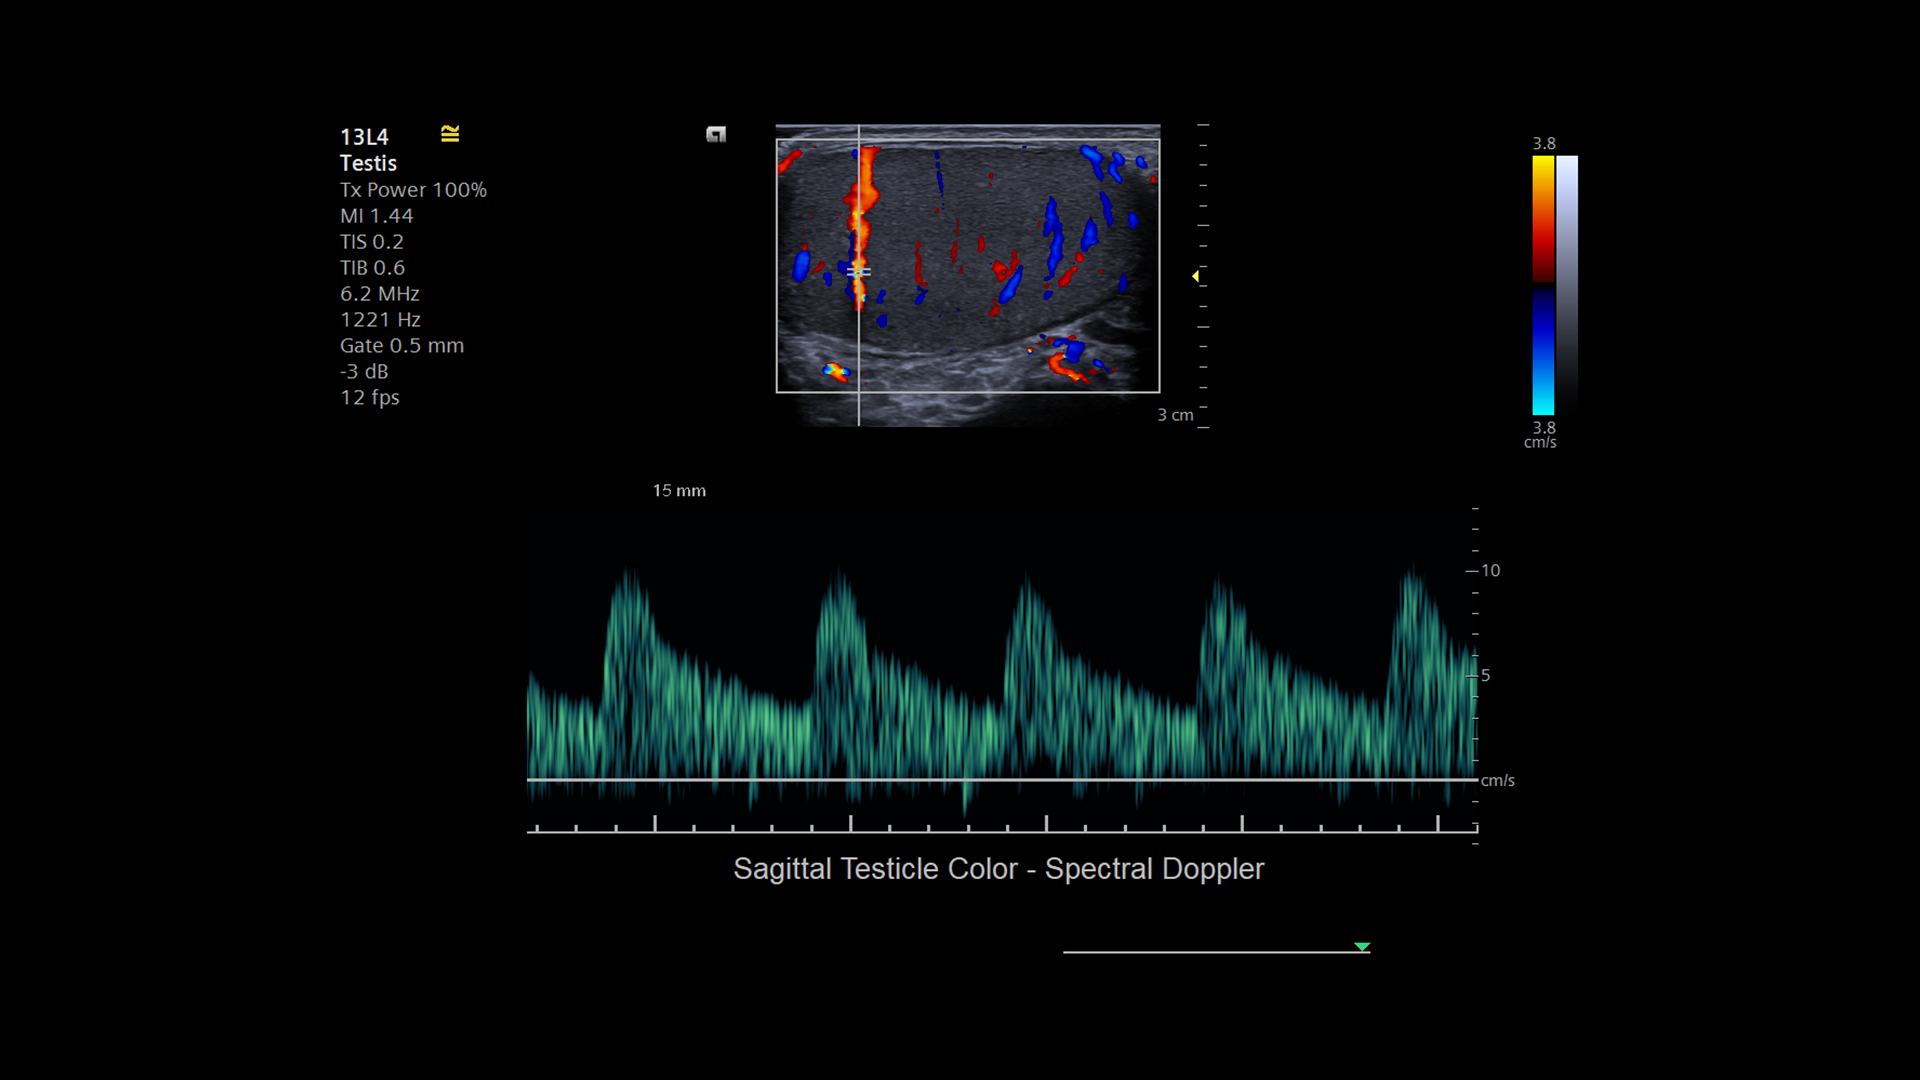

11-13L4-SagTestColorSpectDoppler